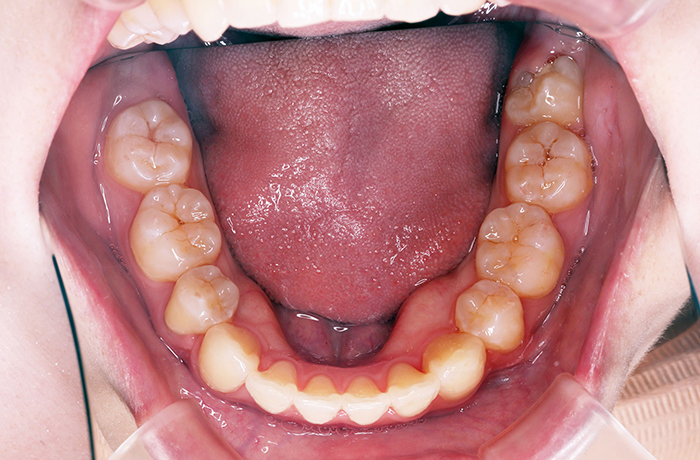

K様

治療前

年齢 27歳

性別 女性

治療名称 マウスピース型カスタムメイド矯正歯科装置(インビザライン)・コンプリヘンシブパッケージ(フルパッケージ)

総額治療費用 770,000円(税込10%) 金額備考 精密検査料・診断料 33,000円(税込10%)

治療期間 1年11か月 通院頻度など 40日ごと

その他治療に関する情報

1枚につき10日装着を指示しました。

治療内容

患者の症状 上顎前歯の前突、八重歯

治療方法 上下左右の第一小臼歯抜歯で、マウスピース型カスタムメイド矯正歯科装置による矯正

治療結果 上顎前歯の前突、八重歯が改善されました。

歯並びをより良くするために追加でアライナーを発注しました。

治療を行う上での注意点

リスク/副作用 決められた時間装着する必要があります。